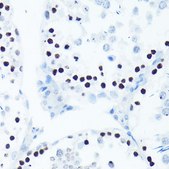

Anti-Phospho-Histone H2AX-S139 antibody produced in rabbit

immunohistochemistry: 1:50-1:200, western blot: 1:500-1:2000

phosphorylation (pSer139)

A synthesized peptide derived from human Phospho-Histone H2A.X (S139).